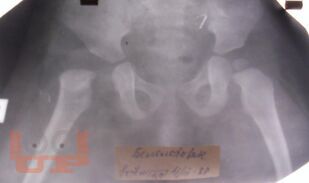

В сборнике трудов представлены публикации сотрудников кафедры травматологии и ортопедии Казанской государственной медицинской академии и научно-исследовательского отдела Республиканской клинической больницы, изданные в 2012–2017 гг., по основным разделам травматологии и ортопедии.

В часть II сборника вошли статьи, ранее опубликованные в журналах, рецензируемых ВАК Минобрнауки, посвященные проблемам хирургического лечения последствий повреждений и ортопедических заболеваний у взрослых и детей.